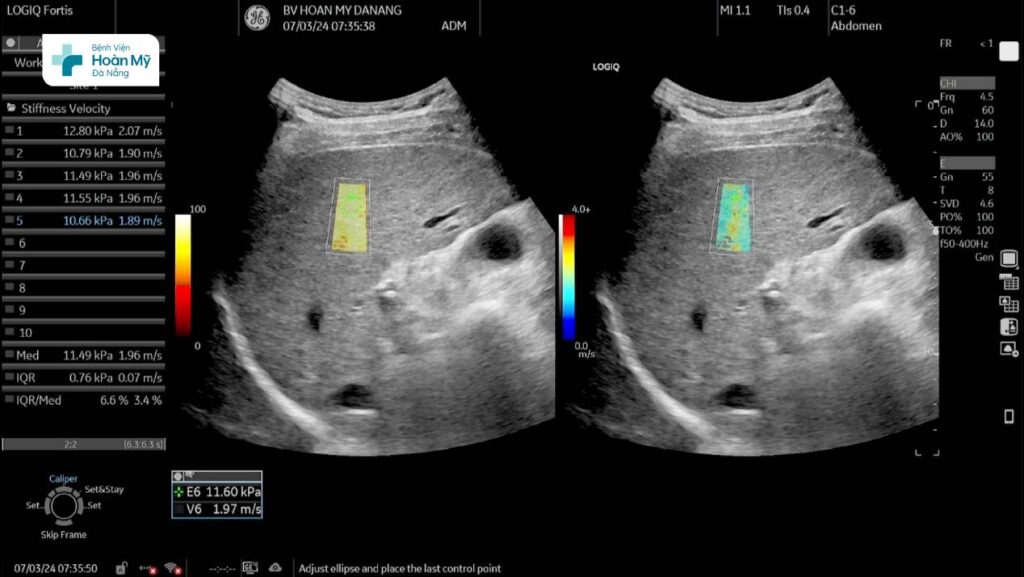

Hình ảnh siêu âm chẩn đoán mức độ xơ hóa gan trên máy siêu âm cao cấp LOGIQ Fortis thế hệ mới tại BV Hoàn Mỹ Đà Nẵng

Một ví dụ khi ứng dụng siêu âm đàn hồi mô trong chẩn đoán xơ gan như sau: Một người bệnh nam, gần đây thấy mệt mỏi nên đến khám tại Bệnh viện Hoàn Mỹ Đà Nẵng, được bác sĩ cho siêu âm bụng, trên siêu âm thường quy thấy cấu trúc gan thô, khi thực hiện siêu âm đàn hồi mô gan đo được độ cứng 11,49 kPa (IQR/Med # 6,6%) tương ứng xơ hóa gan độ 3.

- Đo ít nhất 5 lần, lấy giá trị trung vị (median), đảm bảo IQR/ Med đạt yêu cầu.

- Độ cứng gan được so với bảng tham chiếu để xác định mức độ xơ hóa gan.